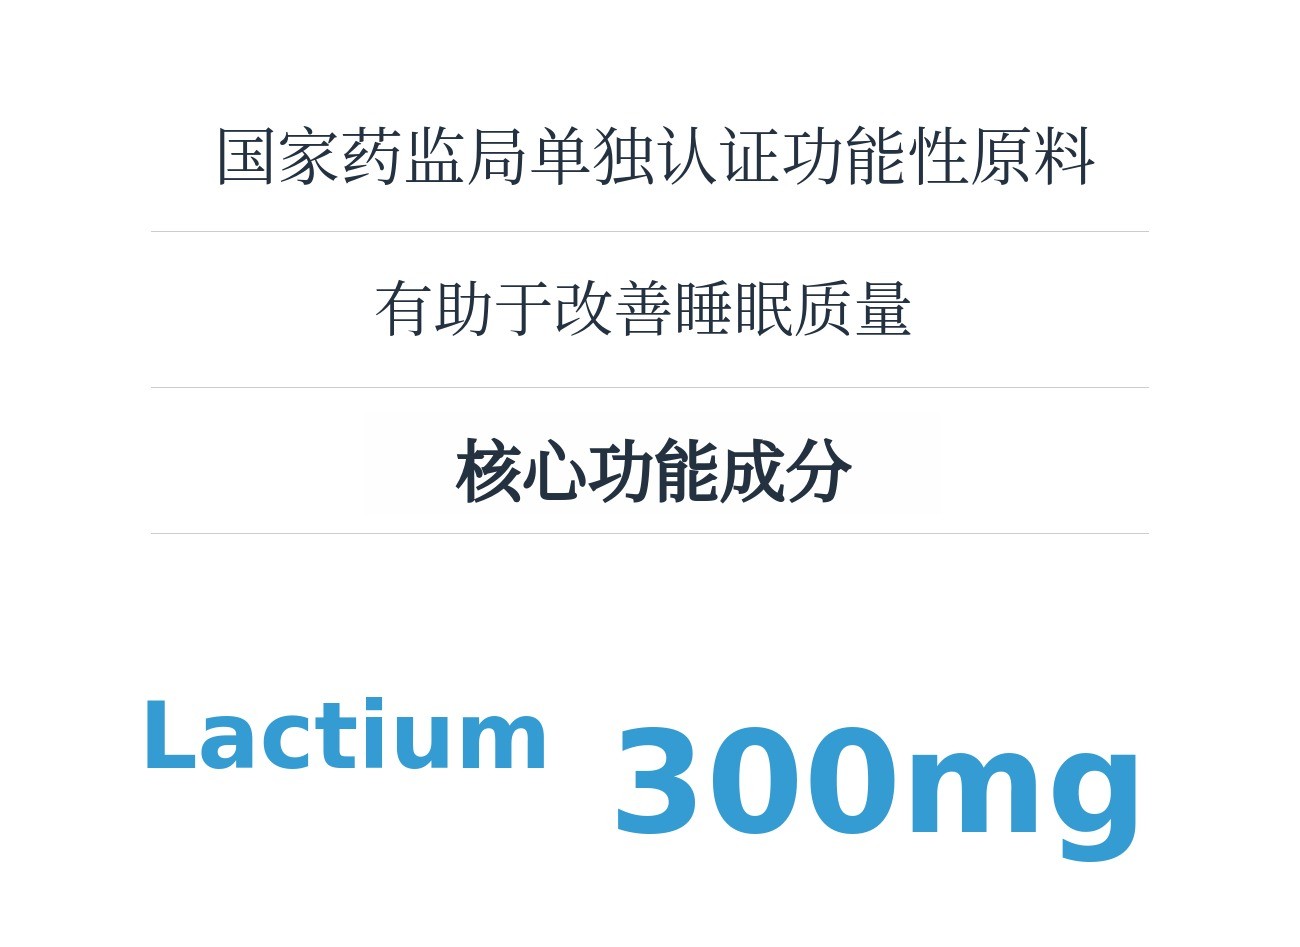

‘MindVita’是以MindCafe积累的咨询数据和临床经验为基础,能够更简单安全地管理压力、情绪管理、睡眠等日常心理问题的健康功能食品品牌。本次通过Wadiz介绍的‘MindVita睡眠Lactium’是由守护数百万心理健康十年的心理健康平台MindCafe与精神健康医学科专家共同研究配比开发的心理护理睡眠营养补充剂。

主要成分Lactium 是通过酶分解牛奶蛋白获得的乳蛋白水解物,属于天然成分,能够抑制压力激素皮质醇的过度分泌,缓解紧张和焦虑,带来心理安定感。同时通过与大脑GABA受体的间接作用,温和降低妨碍睡眠的觉醒状态,无嗜睡或依赖性,自然引导入睡是其特点。